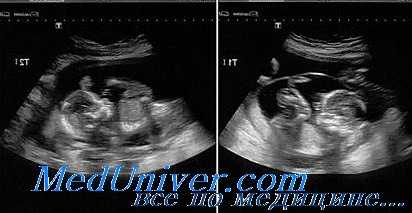

Диагностика многоплодия

Основным методом диагностики на ранней стадии является ультразвуковое исследование. При проведении исследования уже на 5й неделе можно обнаружить 2 или более плодных яйца, располагающихся в полости матки. На более поздних сроках можно увидеть структуру эмбрионов.

Перечисленные симптомы - повод для того, чтобы заподозрить многоплодие. Диагноз в обязательном порядке необходимо подтвердить с помощью УЗИ, ибо только данное исследование является достоверным.